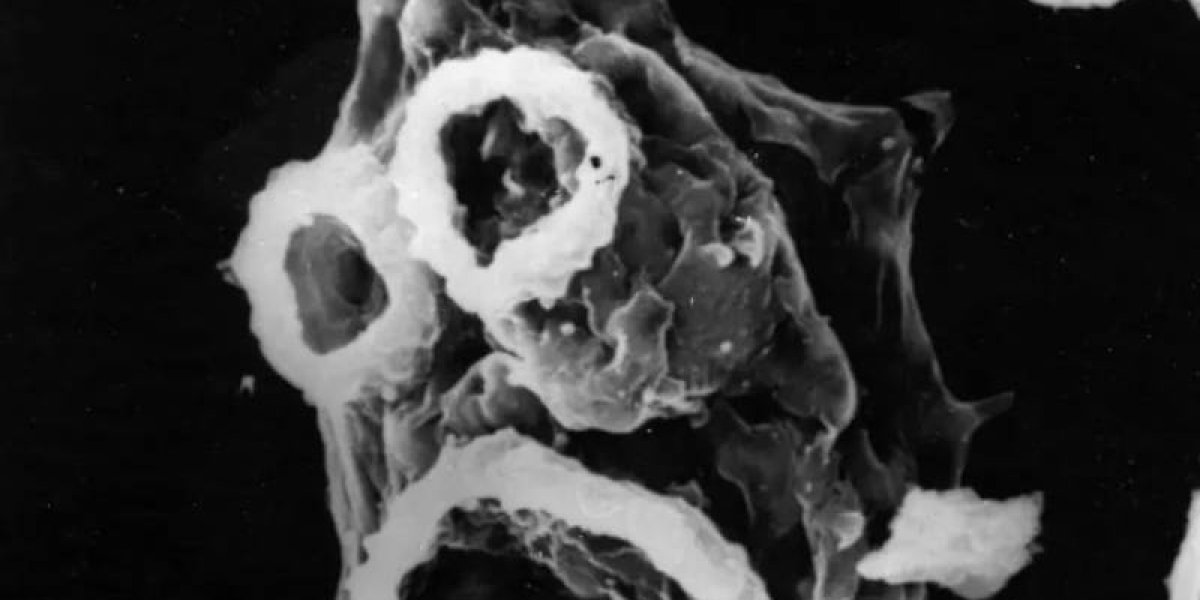

Naegleria fowleri — это редкий и опасный вид амебы, который может вызывать заболевание, называемое примитивным амебным менингоэнцефалитом (PAM). Эта амеба обычно обитает в пресных водоемах, таких как озера, реки и горячие источники.

Человек может заразиться Naegleria fowleri, когда контаминированная вода попадает в нос через носовые проходы, например, во время плавания или погружения в воду. Затем амеба может проникнуть в мозг через нервные пути и вызвать инфекцию, которая часто прогрессирует быстро и может быть смертельной.